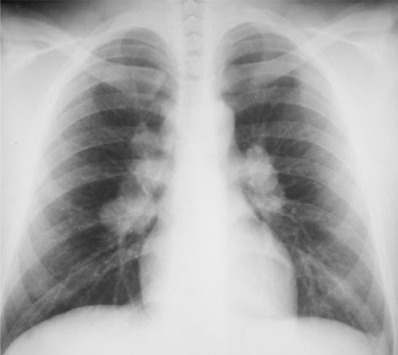

Sarkoidoz, özellikle bedensel aktiviteler sırasında ya da sonrasında genel anlamda bir yorgunluğa, ateş ve nefes darlığına sebep olabilir. Sarkoidoz hastalığının ilk dönemlerinde genellikle hastalık belirtiler gözlenemez. Bu da geç tanıya sebebiyet verir. Genelde başka bir sebeple akciğer filmi çektirildikten sonra sarkoidoz hastalığından şüphelenebilir. Bundan emin olabilmek için ise fiberoptik bir bronkoskop ile akciğerden biyopsi örneği alınır.